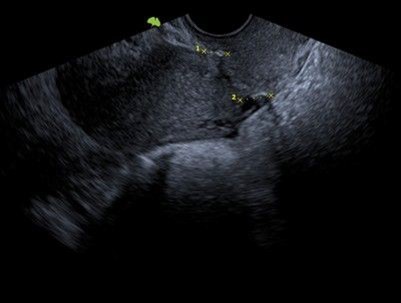

A 36-year-old female patient, G2 P1 A1, with no significant medical history. Her first pregnancy ended with a cesarean section at 27 weeks due to cervical incompetence, with a newborn weighing 850 g. She subsequently suffered an incomplete miscarriage at 19 weeks, also secondary to cervical incompetence, resolved by instrumental uterine curettage. Given the clear history of cervical incompetence, a laparoscopic transabdominal Benson-Durfee cerclage was performed. The procedure was performed without complications, the procedure lasted 60 minutes, a V Care type uterine mobilizer was used, with an estimated blood loss of 100 ml, and she was discharged the following day. Subsequently, the patient continued with follow-up and ultrasound confirmed the correct placement of the cerclage. (Figure 1).

Figure 1: Green arrow: correct placement of the cerclage